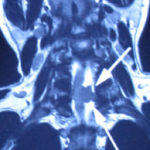

經詳細問症後,很明顯林生的問題已出現馬尾神經綜合症的病況.可能椎管內有腫瘤或腰椎嚴重椎間盤突出壓迫脊髓. 後立刻安排病人照全脊椎磁力共振,並2小時後立即幫病人看片, 果然發現病人頸椎6/7節椎管位置長了一個1.6cm腫瘤嚴重地壓著脊髓. 當日立即轉介至腦神經外科醫生,並安排當晚入院,第二日做割除頸椎管腫瘤手術. 病人術後,腳痛及痲痺,腳部乏力也徐之而改善.

腫瘤嚴重地壓著脊髓